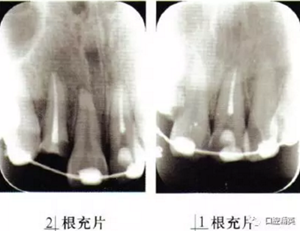

外傷后1周復(fù)查,電活力測試11:47,21:80,22:50,23:50,11RCT,根充恰填(圖3)。外傷后1個月拆除固定(圖4),電活力測試11:45,22:50,23:49。發(fā)現(xiàn)斗絲均為叩痛(±),松I°,2叩痛(一),不松。

圖3 21根充片